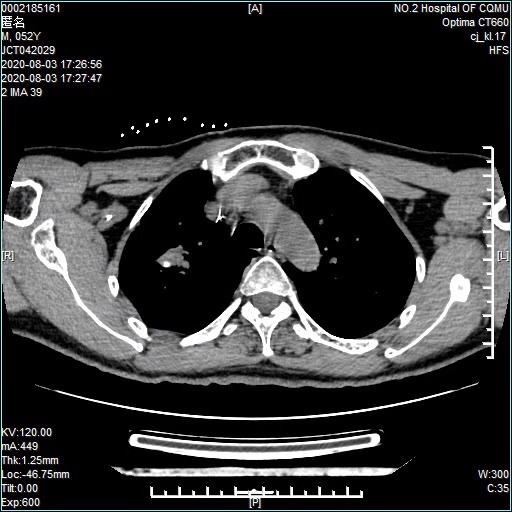

2019年10月,家住丰都的郑先生因不明原因的胸痛、咳嗽,来到重医附二院找到江德鹏诊治。通过CT等检查,明确诊断为肺腺癌,伴淋巴结、骨转移,情况不容乐观。

(术前)

看着一筹莫展的郑先生和他妻子,江德鹏教授安慰他们不用怕,详细解释了肺癌治疗的各种方法,因不适合手术治疗,同时经过基因筛查,发现明确有基因突变后,制订靶向药物联合抑制血管生成药物的治疗方案,同时辅以锶89等治疗。3个月后,认真配合治疗的郑先生复查,肿瘤显著缩小了,病情处于相对稳定状态。